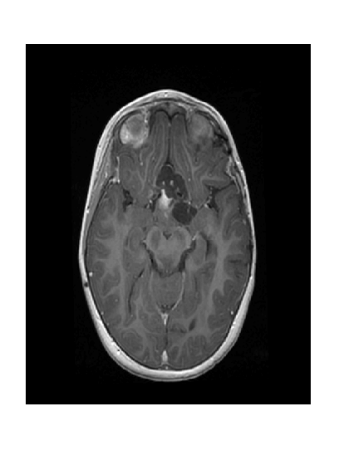

Figure 2: Image reconstruction from Case 20 (a, b, and c) and Case 3 (e, f, and g) of a brain image. Case 20 is the best performing algorithm that uses L1-W and case 3 is the best performing algorithm that uses LACS-MRI

The phantom image that we used in the previous experiment is flat and has less texture while the brain images has a lot of wrinkles and complex shapes. While the phantom image is small, the brain image is too large to calculate fNDsubscript𝑓𝑁𝐷f_{ND} efficiently. Thus, we conducted an experiment in the same setting as the phantom image excluding cases using fAsubscript𝑓𝐴f_{A}: cases 6 through 8 and 14 through 16. In this experiment, contrary to results for the phantom image experiment, L1-W performs better than LACS-MRI. For example, Case 3 performed the best among cases using LACS-MRI but it performs worse than 6 cases that use L1-W. Interestingly, one of the cases that shows an outstanding image recovery purely uses fVDSsubscript𝑓𝑉𝐷𝑆f_{VDS} with L1-W. However, purely using fVDsubscript𝑓𝑉𝐷f_{VD} with L1-W shows a dramatically worse performance. In conclusion, we are unsure why each combination of mixed PDFs and reconstruction algorithm perform differently based on the images processed, but this differing behavior is crucial to highlight for practical applications. We conjecture that the texture of the image is one factor that decides the performance of each algorithm. In the future, we may explore this conjecture and analyze why this happens.